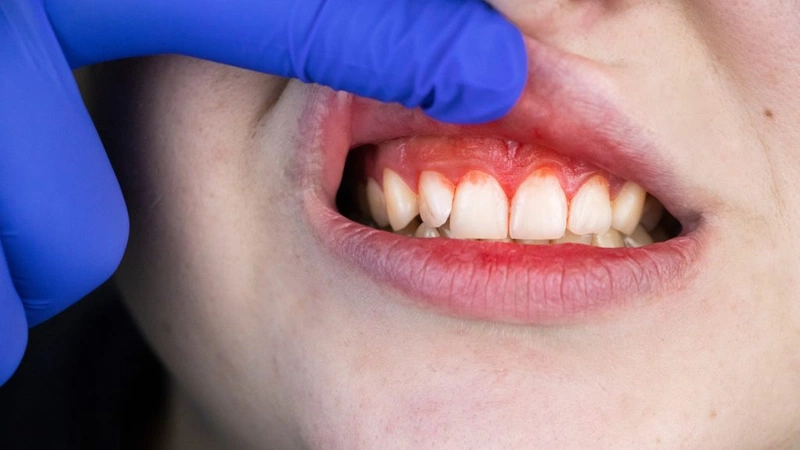

- 황달 : 피부와 눈의 흰자위가 노랗게 변함

- 출혈 경향 : 쉽게 멍이 들거나 출혈이 발생할 수 있음

- 거미혈관종 : 피부에 거미 모양의 붉은 반점이 나타남